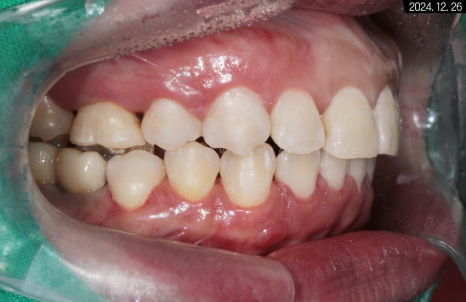

유지장치를 부착하고 난 후의 악궁 사진입니다.

수평 피개가 해소되었기 때문에

측면에서 봐도 중심선이 바릅니다.

둥글게 변하면서

교합 상태가 이상적인 모습을 보이네요.